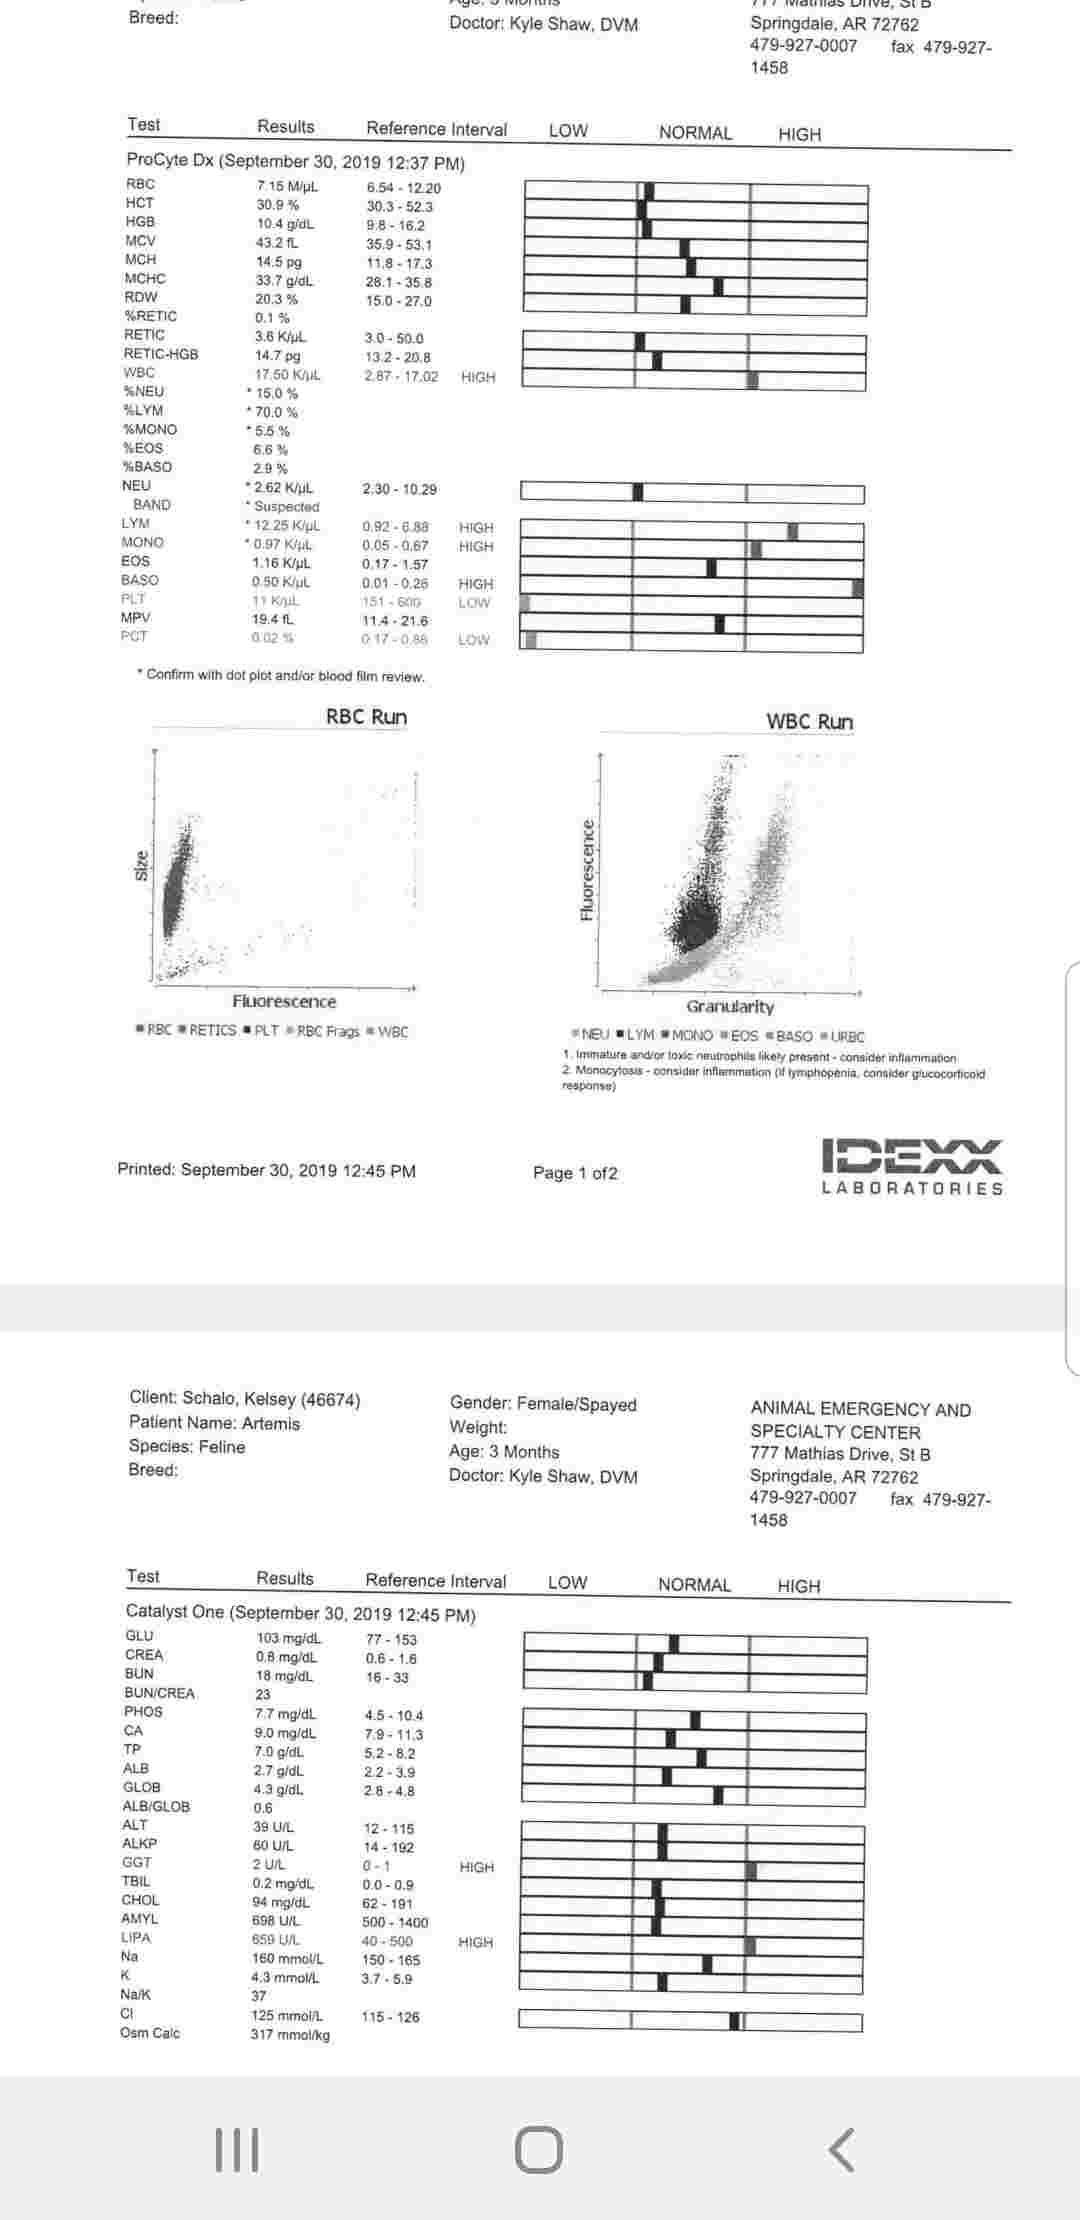

Artemis has had diarrhea periodically since adoption. She's had multiple fecal tests (always negative) and has been fully dewormed and treated for coccidia to be safe. She has had blood tests and xrays. She has had antibiotics and probiotics. Is it possible her science diet kitten food is doing this? Should I be concerned by this? She is still eating, drinking, and playing with her brother. Should I just buy her more probiotics? I've attached her labs from a month ago.